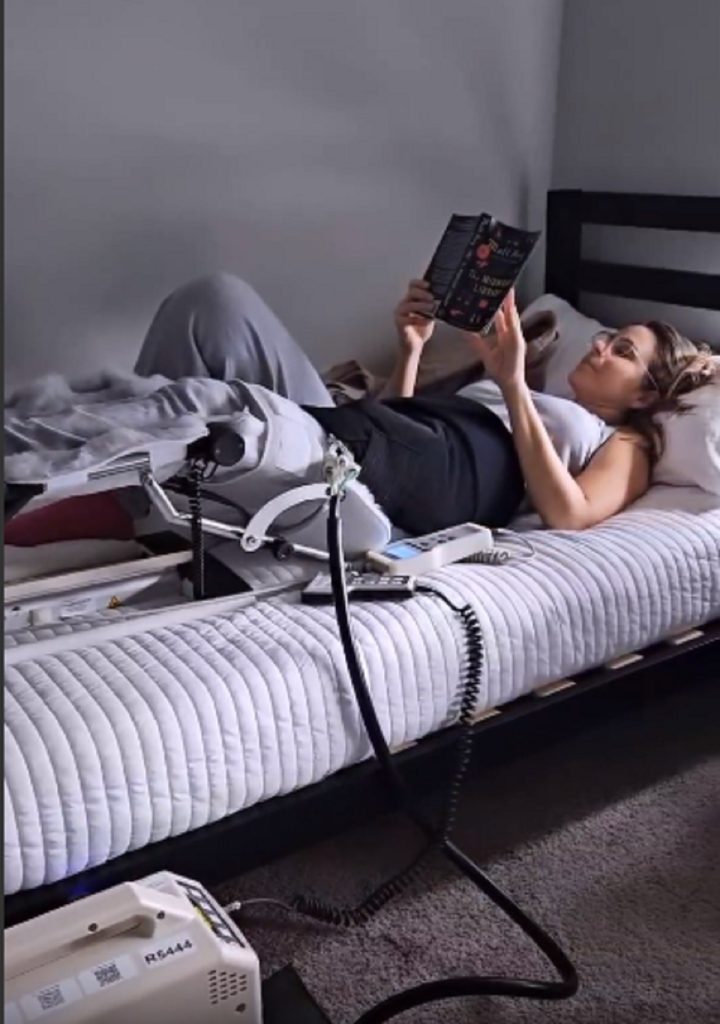

La esposa del actor Luciano D’Alessandro contó que se decidió por la cirugía luego de experimentar mucho dolor durante varios meses, encontrarse casi siempre medicada y luego de consultar a varios médicos.

Afortunadamente, el procedimiento se realizó sin contratiempos. “La cirugía fue un éxito, todo quedó como debía y aunque pase momentos nada buenos (que contaré después), ya estoy mejor, recobrando la fuerza para retomar todo nuevamente, pero con el aprendizaje de seguir entendiendo la fragilidad de la vida, de llevar las cosas con más calma y sobre todo agradeciendo las bendiciones, entre ellas poder seguir compartiendo y disfrutando de cada momento con los que amo”, destacó en el post que compartió, en el que incluyó un video que resume parte del proceso que pasó.

Si bien María Alejandra Requena, de 49 años de edad, admite que es muy joven para este tipo procedimientos, señala también que una vida sin dolor no es vida.

La autora caraqueña también tuvo palabras de agradecimiento para su médico (Dr David Maldonado), quien “estuvo muy pendiente de mi recuperación, tanto que hasta me visitó y me escribía a diario para saber de mi salud y como me sentía”.